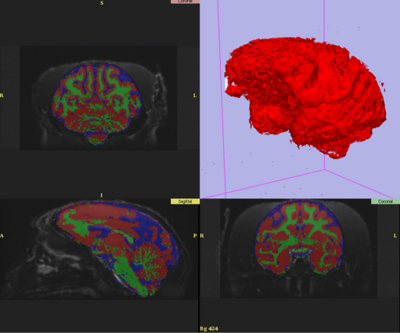

- Optimize the EM Brain Classifier in Slicer on MRI images of rhesus macaques

- Develop a custom GM/WM/CSF atlas, bootstrapping from one provided by Martin Styner

- Nonlinear registration of atlas priors completed using Slicer

- Full EM segmentation model accommodating severe coil inhomogeneity completed

- EMSegmenter parameters partially optimized for a single subject